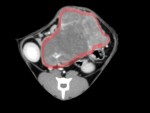

レントゲン検査およびエコー検査を実施したところ、上腹部に直径約6.5cm大の巨大な腫瘤と胸腔内にも腫瘤を認めた。

後日精査するためにCT検査およびFNA検査を実施し、消化管型リンパ腫と診断できた。胸腔内の腫瘤は胸骨リンパ節の腫大と考えられ、その他のリンパ節も多数腫大していることが分かった。現在、化学療法を実施中である。治療後1週間の腫瘤は、腹部触診では殆ど触知できないまで縮小し、生活の質は向上している。